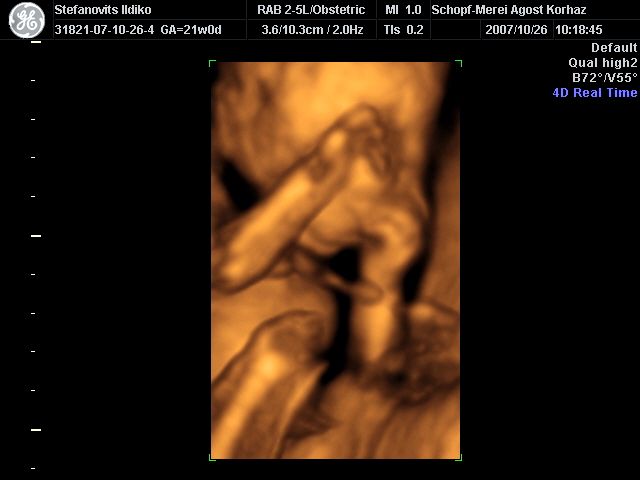

4D Ultrahang - 21+1 (07/10/26, Bp.)

4D - 1